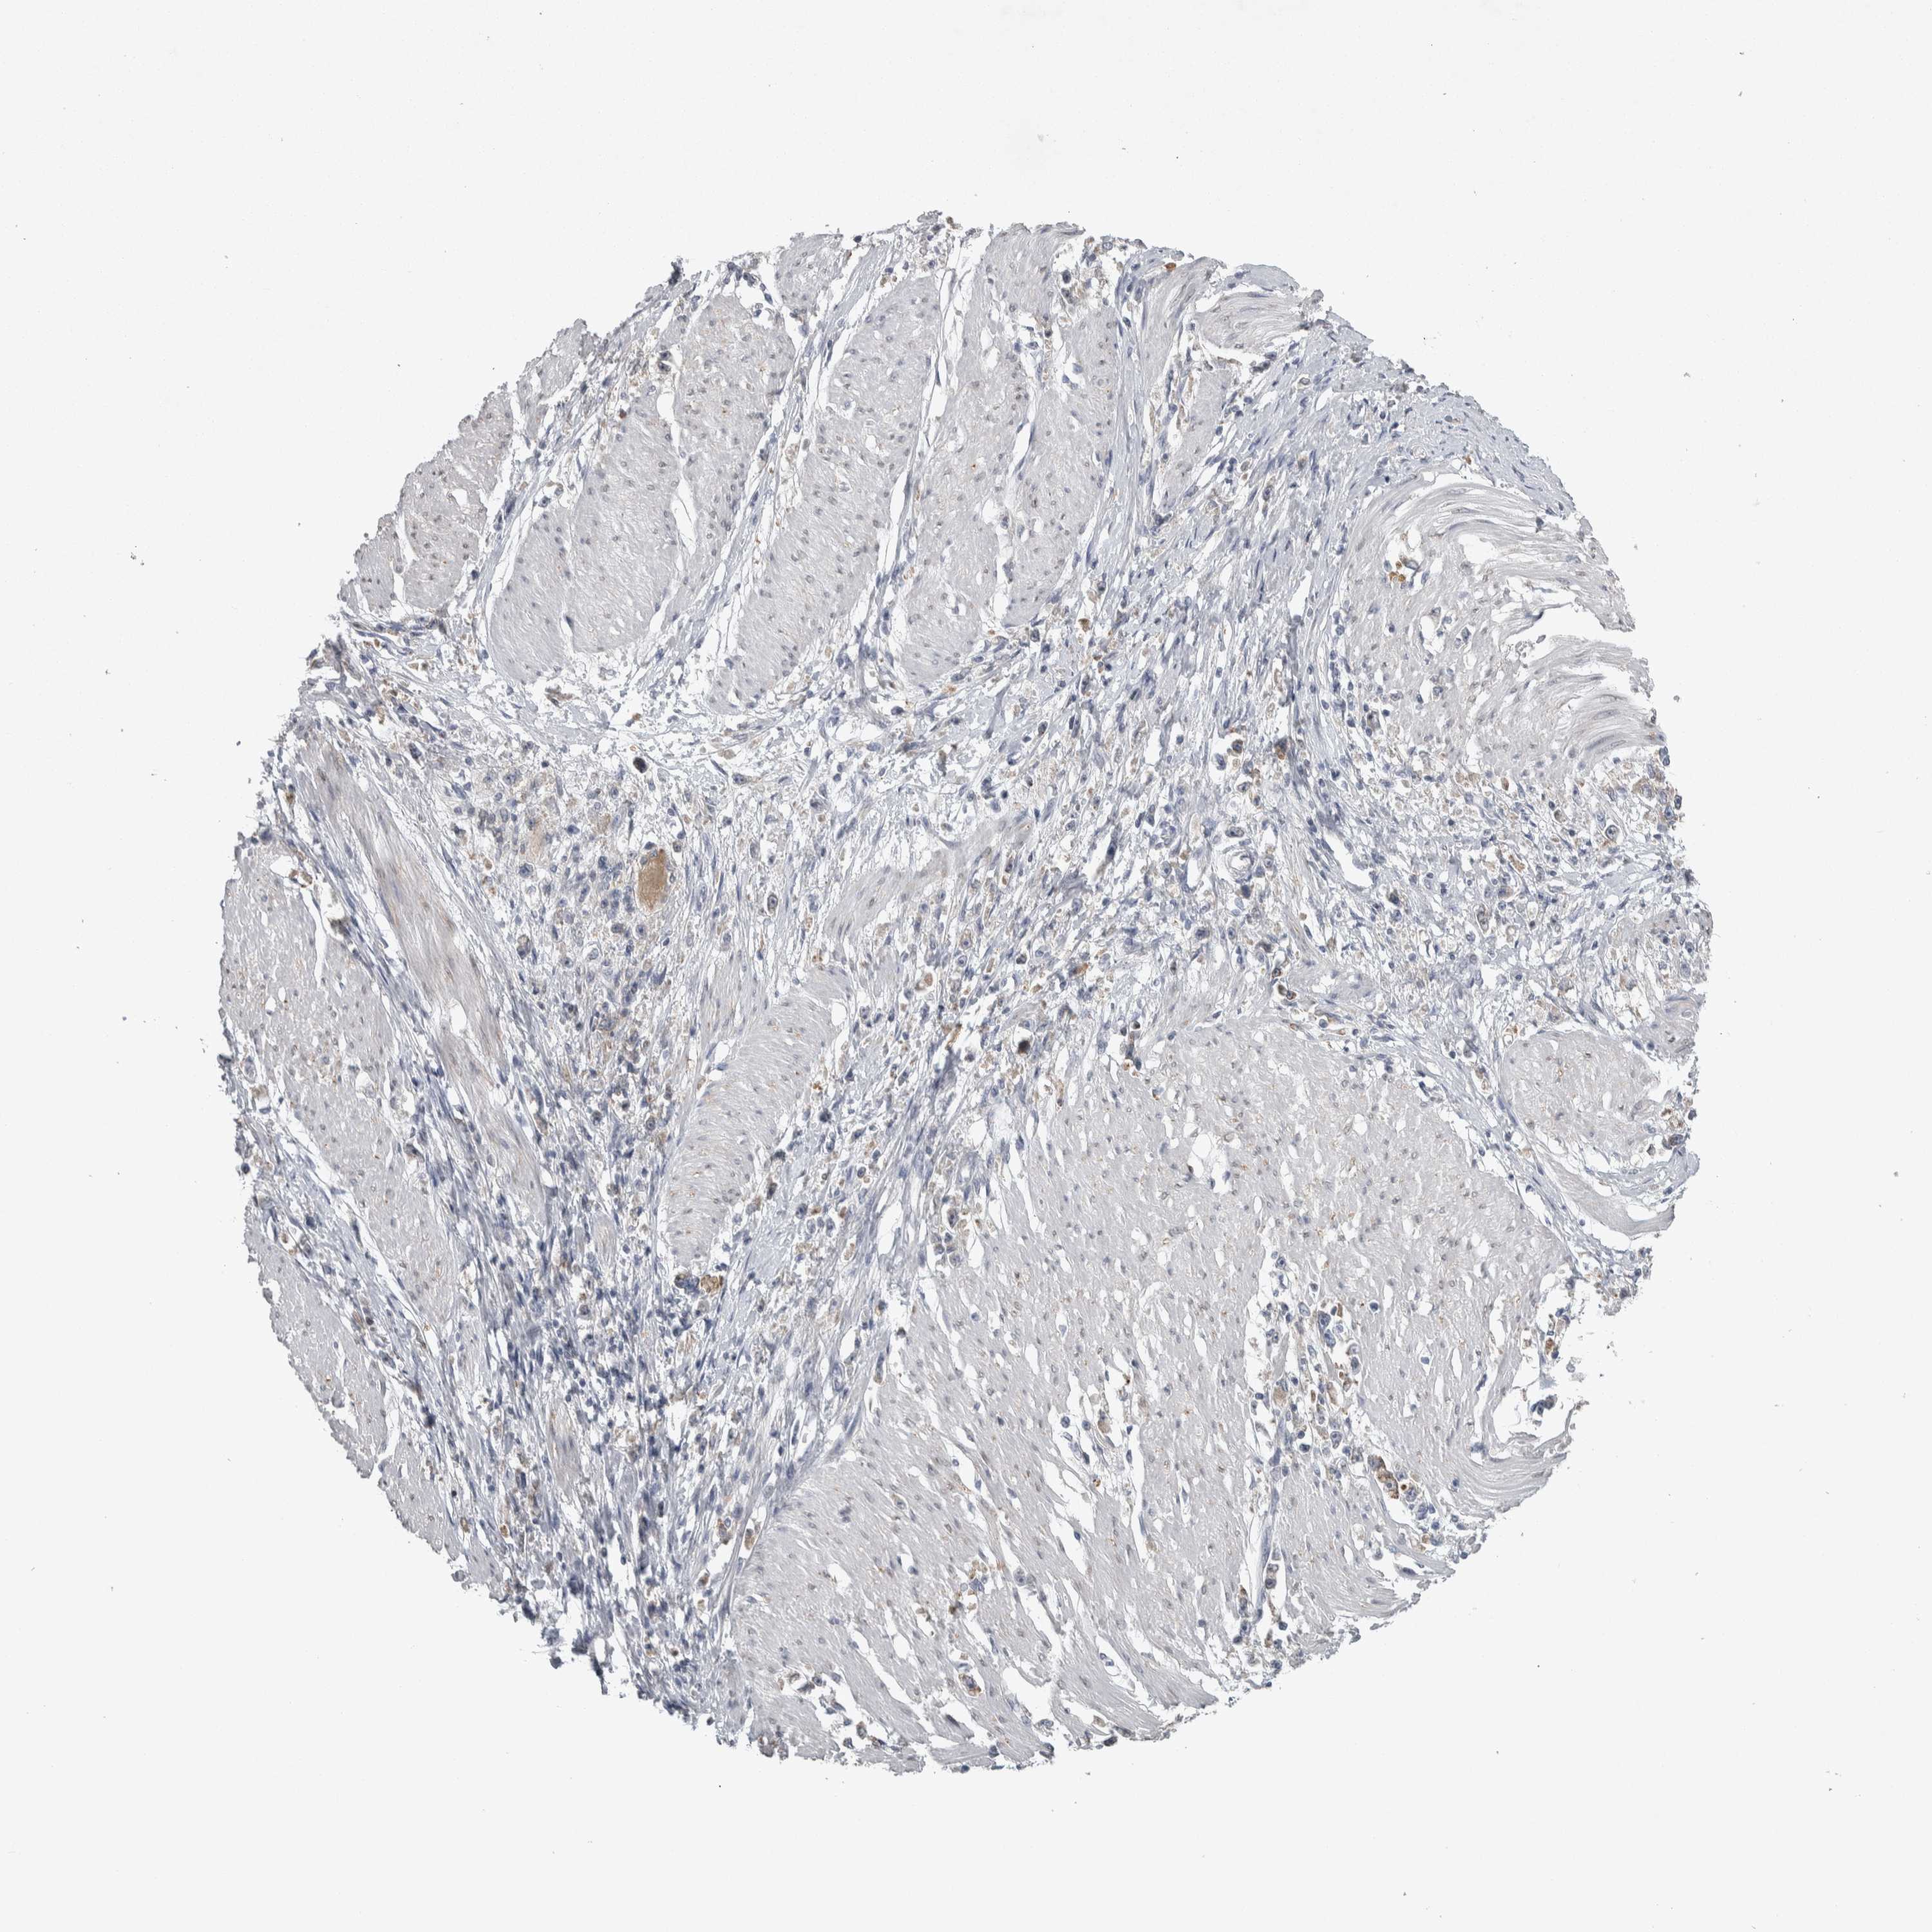

STOMACH CANCER - Protein expressioni

A mouse-over function shows sample information and annotation data. Click on an image to view it in a full screen mode. Samples can be filtered based on level of antibody staining by selecting one or several of the following categories: high, medium, low and not detected. The assay and annotation is described here.

Note that samples used for immunohistochemistry by the Human Protein Atlas do not correspond to samples in the TCGA dataset.

Antibody stainingi

Antibody staining in the annotated cell types in the current human tissue is reported as not detected, low, medium, or high, based on conventional immunohistochemistry profiling in selected tissues. This score is based on the combination of the staining intensity and fraction of stained cells.

Each image is clickable and will lead to virtual microscopy that enables deeper exploration of all samples and also displays staining intensity scores, fraction scores and subcellular localization as well as patient and tissue information for each sample.

Antibody HPA018002

Antibody HPA024071

Antibody CAB013470

Staining

High

Medium

Low

Not detected

Intensity

Strong

Moderate

Weak

Negative

Quantity

>75%

75%-25%

<25%

None

Location

Nuclear

Cytoplasmic/membranous

Cytoplasmic/membranous,nuclear

Adenocarcinoma, NOS

Adenocarcinoma, High grade